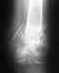

Перелом левой пяточной кости со смещением

Здравствуйте!Меня зовут Михаил. Мне 23 года, рост 175 см, вес 75 кг. 17.11.2009 упал с высоты, попал в больницу с диагнозом перелом левой пяточной кости со смещением. Была большая опухоль в области лодыжки, спустя 2 недели опухоль прошла и наложили гипс до колена под углом 90 градусов между голенью и стопой. 11.02.2010 сняли гипс. Из за некомпетентности местных врачей поехал в нижегородский институт травматологии и ортопедии. Назначали ЛФК, кроссовки, ступинаторы.ЛФК начал заниматься последние 4 дня, жалуюсь на значительные боли, до сих пор передвигаюсь с помощью костылей при попытки наступание на носок острая боль в области архилесого сухожилия, при попытки наступание на ступню острая боль в области пятки. Снимки прилагаются + сегодняшние фотографии ноги.Требуется квалифицированная помощь. И возникает вопрос буду ли я годен в армию. переживаю за неправильную геометрию с задней стороны ноги.снимки 17.11.2009 до гипсаhttp://s45.radikal.ru/i109/1003/2d/bb1a2d28eb0a.jpghttp://s39.radikal.ru/i085/1003/51/8ec7a702f6c7.jpgснимки 03.03.2010 после гипсаhttp://i015.radikal.ru/1003/92/9f229ea760c2.jpghttp://s58.radikal.ru/i162/1003/f8/1957b396bb06.jpgфотографии ноги на сегодняшний деньhttp://s19.radikal.ru/i192/1003/29/58efe0c3bf4b.jpghttp://s001.radikal.ru/i194/1003/bf/ba87e1b68004.jpghttp://i074.radikal.ru/1003/ff/503ccdce2995.jpghttp://s58.radikal.ru/i159/1003/9a/8000b52fa132.jpgЗаранее благодарен.